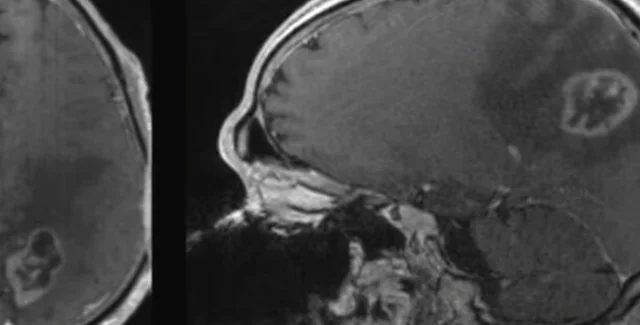

МРТ-изображение глиобластомы | Фото: Dominique Higgins, MD, PhD

Глиобластома является невероятно агрессивной, распространенной и смертельной формой рака мозга, на ее долю приходится 15% смертей. Стараясь найти эффективный способ ее лечения, ученые из Школы медицины Университета Северной Каролины (УСК) убрали определенные аминокислоты из питания подопытных мышей и обнаружили, что ферроптоз, являющий собой форму некроза, при которой в клетке накапливаются перекиси липидов, запустил смерть разрушительных клеток болезни. Более того, мыши соблюдавшие эту диету были гораздо более восприимчивы к лекарственным препаратам, которые так же запускали процесс смерти клеток рака, что сделало данное открытие невероятно интересным с точки зрения нахождения потенциального источника для борьбы с этой смертельной болезнью, пишет New Atlas.

В статье, которую опубликовали ученые, говорится о том, что они выяснили, что клетки глиобластомы особенно подвержены гибели именно от ферроптоза. Они заявили, что это открытие невероятно значимо, так как глиобластома 100% фатальна для больного и не имеет способов лечения. Так же, из-за своей невероятно агрессивной натуры, в среднем она не оставляет больным больше 16 месяцев перед тем как забрать их жизнь.